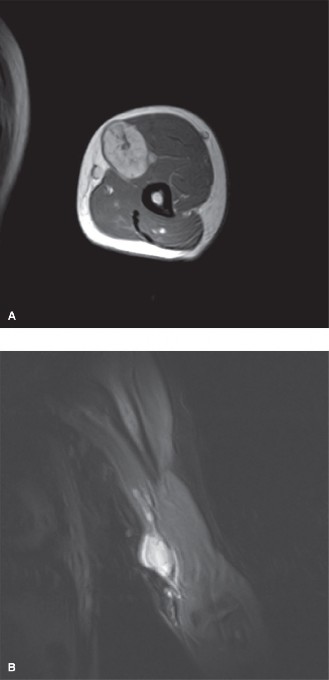

A 46-year-old male presents to you for a second opinion. He recently underwent surgery to remove a mass from …